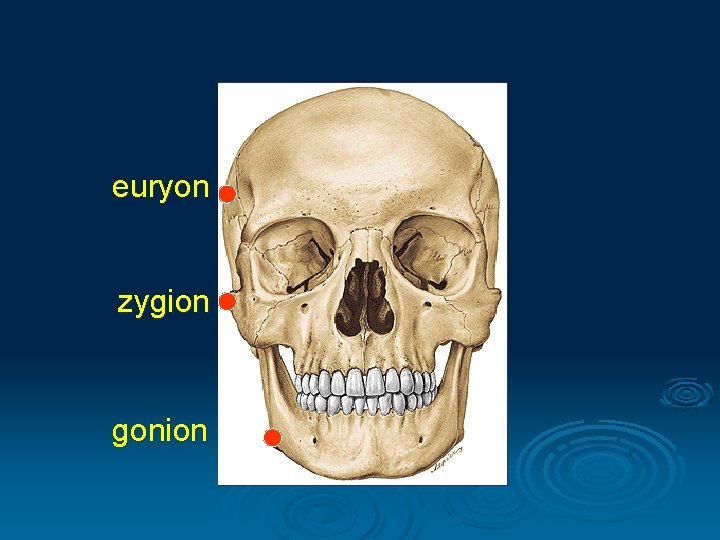

I. Cranimetry Points § Unpaired: nasion, glabella, bregma, akanthion, lambda, orale, opisthocranion, basion, staphylion § Binate: pteryon, porion, euryon, zygion, gonion, endomolare

euryon zygion gonion

Size of the face Length: nasion - gnathion Width: zygion - zygion

Facial index the ratio multiplied by 100 of the breadth of the face to its length Leptoprosopic 90, 9 - x (long narrow face) Mesoprosopic 85, 0 - 89, 9 (average width) Euryprosopic x - 84, 9 (short broad)